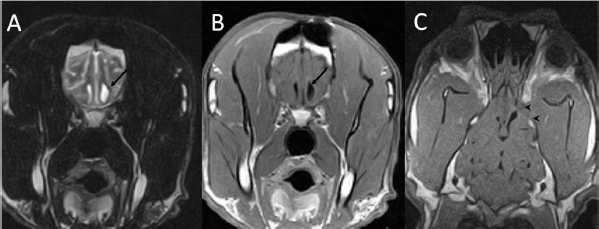

A 3-year-old female Great Dane was referred for acute onset behavioral changes (aggression and disorientation) of 2 weeks duration, and seizures from 24 hours prior to presentation. Physical examination revealed no abnormalities in body temperature, body condition score, heart rate, pulse quality, or cardiopulmonary auscultation. All lymph nodes were considered of normal size and no pain was elicited upon manipulation of the orbital, aural, or cranial musculature. Neither was there any history of dermatological or traumatic lesions in the eye, ear, or mouth. The neurological examination revealed the patient to be obtunded with decreased postural reactions and menace response worse in the left side. Neuroanatomic lesion localization was considered focal in the right prosencephalon with a possible increase in intracranial pressure. Hematological and serum biochemical analysis showed no abnormalities. Magnetic resonance imaging was performed using a low-field magnet (Airis Mate; Hitachi, Tokio, Japan). The study revealed a left-sided single frontal intra-axial lesion affecting gray and white matter adjacent to the internal capsule at the level of the optic canal (Fig. 1). The lesion presented signal homogeneity characterized by hyperintensity on T2W and FLAIR sequences and hypointensity in T1W sequences with peripheral enhancement after intravenous contrast administration (Fig. 1A and 1B). The lesion had a round shape with the greatest diameter of 2.84 cm. This enhancement was also recognized in the surrounding meninges following the brain surface following sulci. A small linear tract observed was directed dorsally from the lesion through the corona radiata (Fig. 1B). The lesion was associated with extensive perilesional vasogenic edema that worsened the mass effect characterized by a midline shift. The orbital and medial pterygoid muscles also showed an intense enhancement (Fig. 2). The wing of the presphenoid bone was thinner than the contralateral bone (Fig. 1B). A CT scan (Astelion 16, Toshiba, Tokio, Japan) was performed after MRI that allowed the identification of osteolysis in the presphenoid bone immediately dorsal to the orbital fissure (Fig. 1C). CT scan also revealed a hypoattenuating intra-axial lesion located in the left frontoparietal lobe together with diffuse hypoattenuation of tissues adjacent to the left optic nerve and the left pterygoid muscle. Finally, CSF analysis showed no abnormalities. On the basis of advanced radiological findings, the main differential diagnosis was an intracranial abscess due to the extension of the extracranial septic process through presphenoid bone. Because of rapid neurologic deterioration and suspected increased intracranial pressure, surgical excision was planned. A modified left rostrotentorial craniectomy was performed. Temporalis muscle and fascia were retracted, extending the incision cranially through the temporal line. Once the frontal and presphenoid bones were exposed an area of osteolysis was observed in the wing of the presphenoid bone immediately dorsal to the orbital fissure. The craniectomy (approximately 3 cm diameter) was centered on the osseous defect. A mucopurulent discharge presented immediately after the incision of the dura mater. A sample was collected for its microbiological study. The surgical site was flushed with sterile saline revealing the tip of a grass awn which was extracted from the brain parenchyma together with a small amount of purulent fluid (Fig. 3). After extensive flushing, the meninges were left open to allow drainage and the incision was closed as per routinely. Postoperative CT showed the correct location of the craniectomy and resolution of the abscess which was substituted by gaseous content but remained inside and on the dorsal surface of the frontal lobe (Fig. 4). Immediate postoperative therapy consisted of amoxicillin + clavulanic acid (Synulox 500, Zoetis Spain SL) 22 mg/kg PO, q8h; marbofloxacin (Marbocyl P80, Vetoquinol SA) 5 mg/kg PO, q24h; metronidazole (Flagyl 250, Sanofi-aventis SA) 15 mg/kg PO, q12h; prednisone (Prednisona Kern Pharma 30mg, Kern Pharma) 0.5 mg/kg PO, q12h; tramadol (Tramadol retard Combix 100 mg, Laboratorios Combix S.L.U) 2 mg/kg PO, q8h; famotidine (Famotidina Normon 40 mg; Laboratorios Normon SA) 0.7 mg/kg PO, q24h; and phenobarbital (Phenoleptil 100 mg, Le Vet BV) 2.5 mg/kg PO, q12h. Cultured samples were positive for Pseudomonas aeruginosa sensitive to ciprofloxacin, imipenem, and amikacin among other antibiotics. Based on these results, antibiotic therapy was changed to ciprofloxacin (Ciprofloxacino 500, Laboratorios Normon SA) 10 mg/kg PO, q12h and metronidazole 15 mg/kg PO, q12h for 2 months. Prednisone, tramadol, and famotidine were withdrawn and phenobarbital was maintained at 2.5 mg/kg q12h. Six-month post-operative revision magnetic resonance revealed no signs suggesting the existence of an inflammatory process (Fig. 5). In the area where the abscess had been located, a fluid-filled cavity suggesting being CSF was observed. One year follow-up revealed the patient had seizures every 3 months with neurological examination remaining normal. The patient died 2 years later of unrelated causes.

Fig. 2. (A) Transverse and (B) dorsal post-contrast T1-weighted images revealing enhancement of orbital musculature and medial pterygoid muscle (arrows).